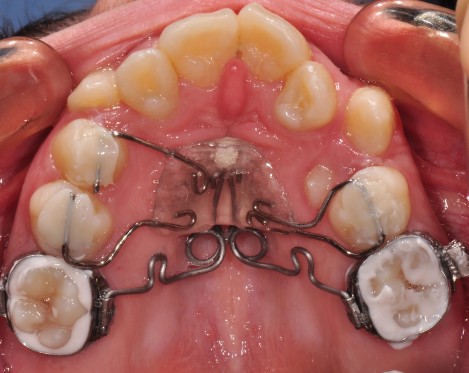

Предимства на методите на лечение с интраоралния фиксиран апарат M-Pendulum

За да се достигне до решение за избор на екстракционно или безекстракционно оротодонтско лечение е необходимо да се съобразим с недостига на място в зъбната дъга и продължителността на лечението. За това си поставихме за цел да съпоставим тези параметри.

Клинични аспекти при прилагане на апарата Pendulum в смесено съзъбие

В тази статия си поставяме за цел да разискваме от клинична гледна точка позитивите и негативите при ползване на апарата Pendulum в смесено съзъбие. Ще разгледаме становищата за работа с апарата в случаите, когато са включени временните молари като опорна зона. Ще дадем какви са според нас клиничните предпоставки и индикации за използването на Pendulum в смесено съзъбие.